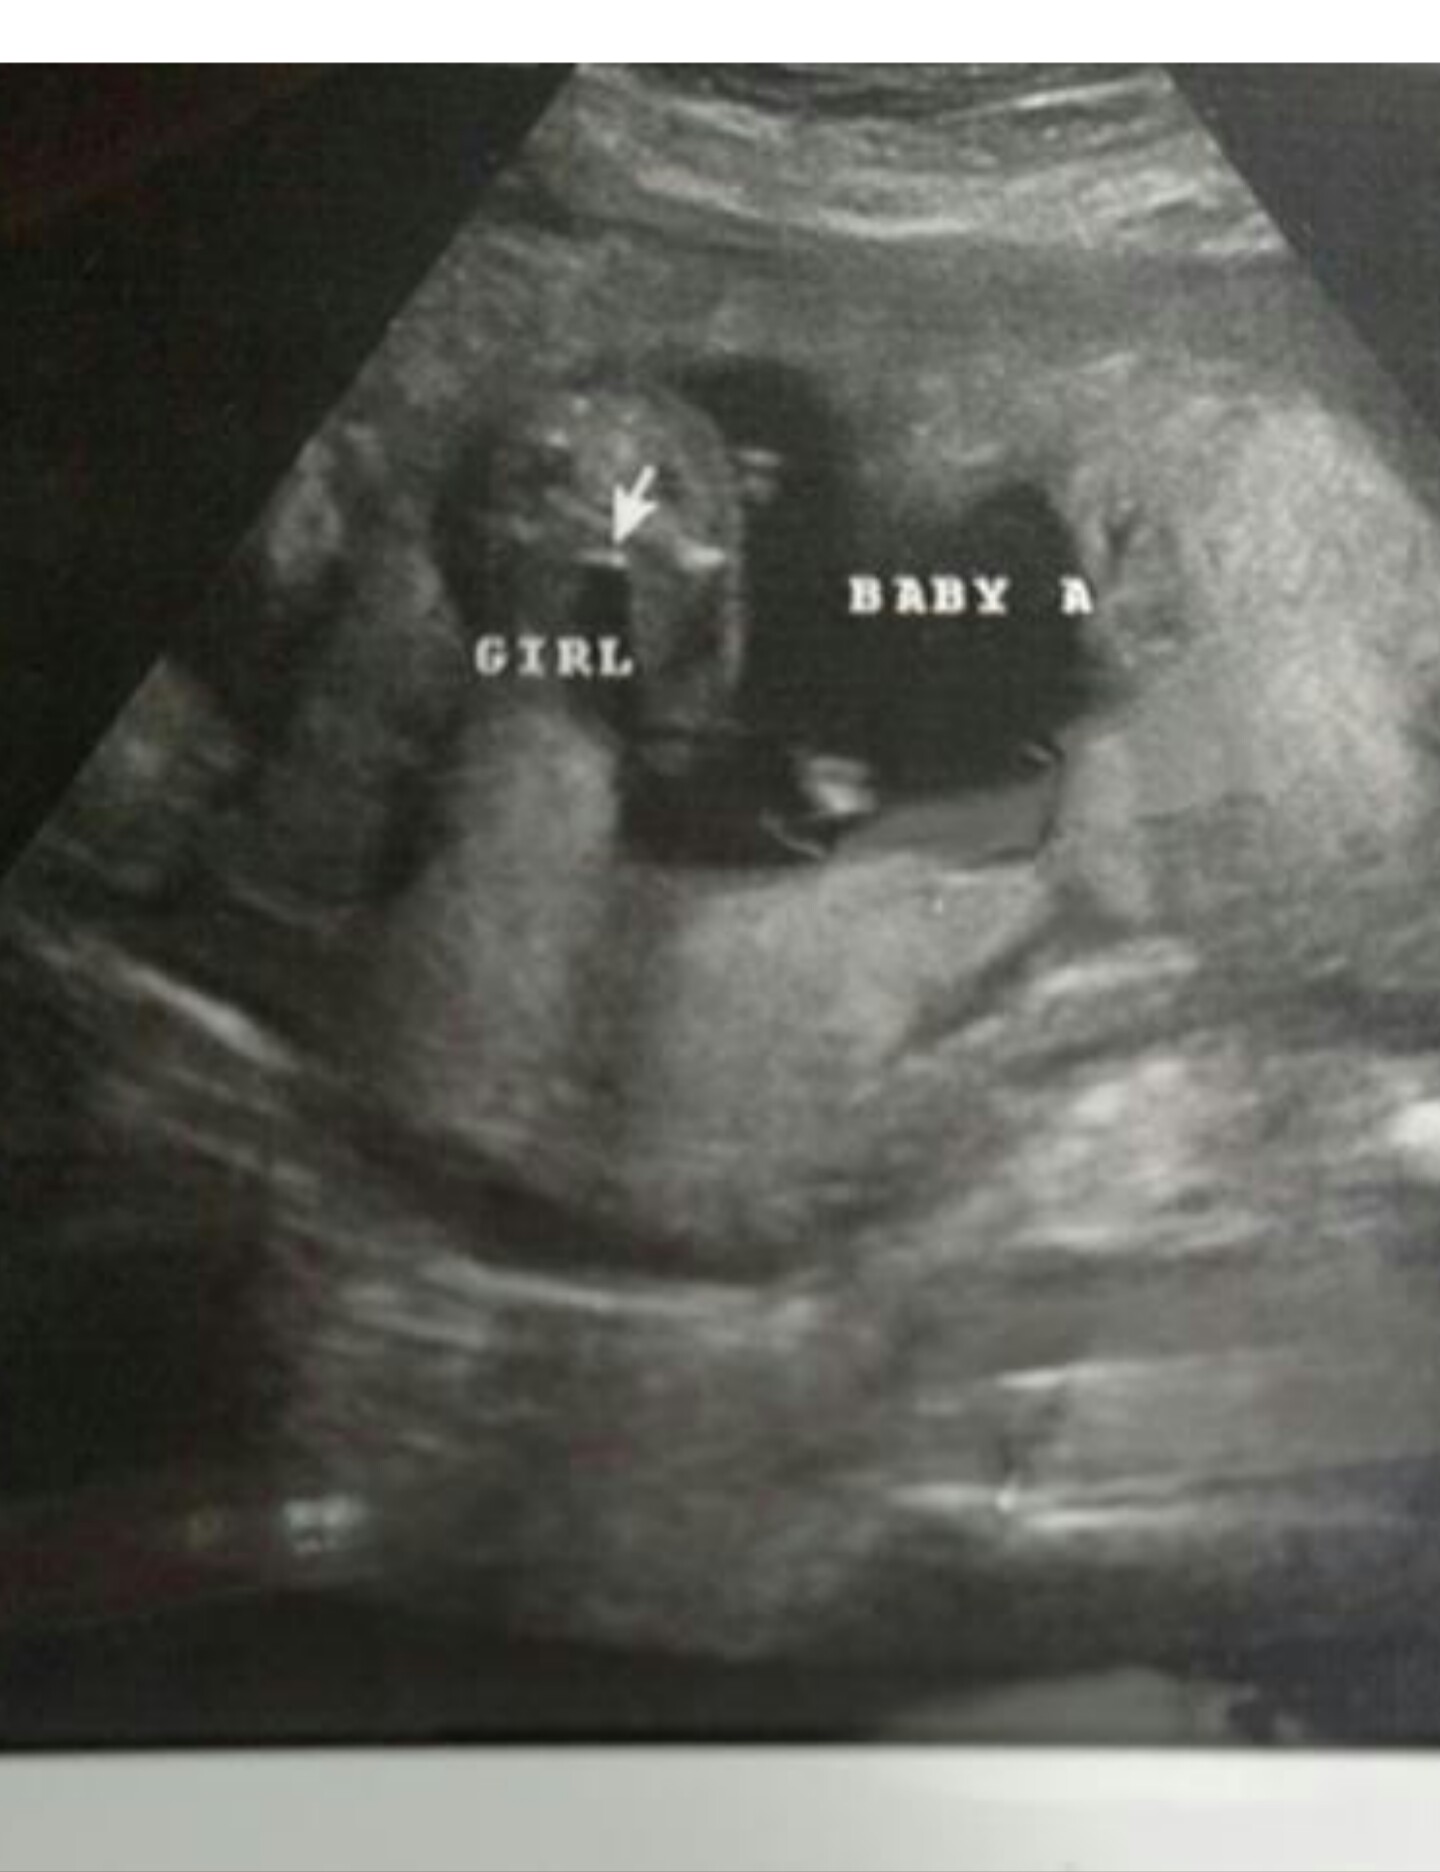

Okay thanks to some help hopefully it will post now! I really don't wanna get my hopes up and really have my heart set on this girl! I have 2 boys and one of the twins is all boy. I don't see the 3 lines everyone is talking about bit she really took her time looking. It was just early and I have my doubts. Any input would be wonderful!! Thanks y'all!!!!Attachment 28094